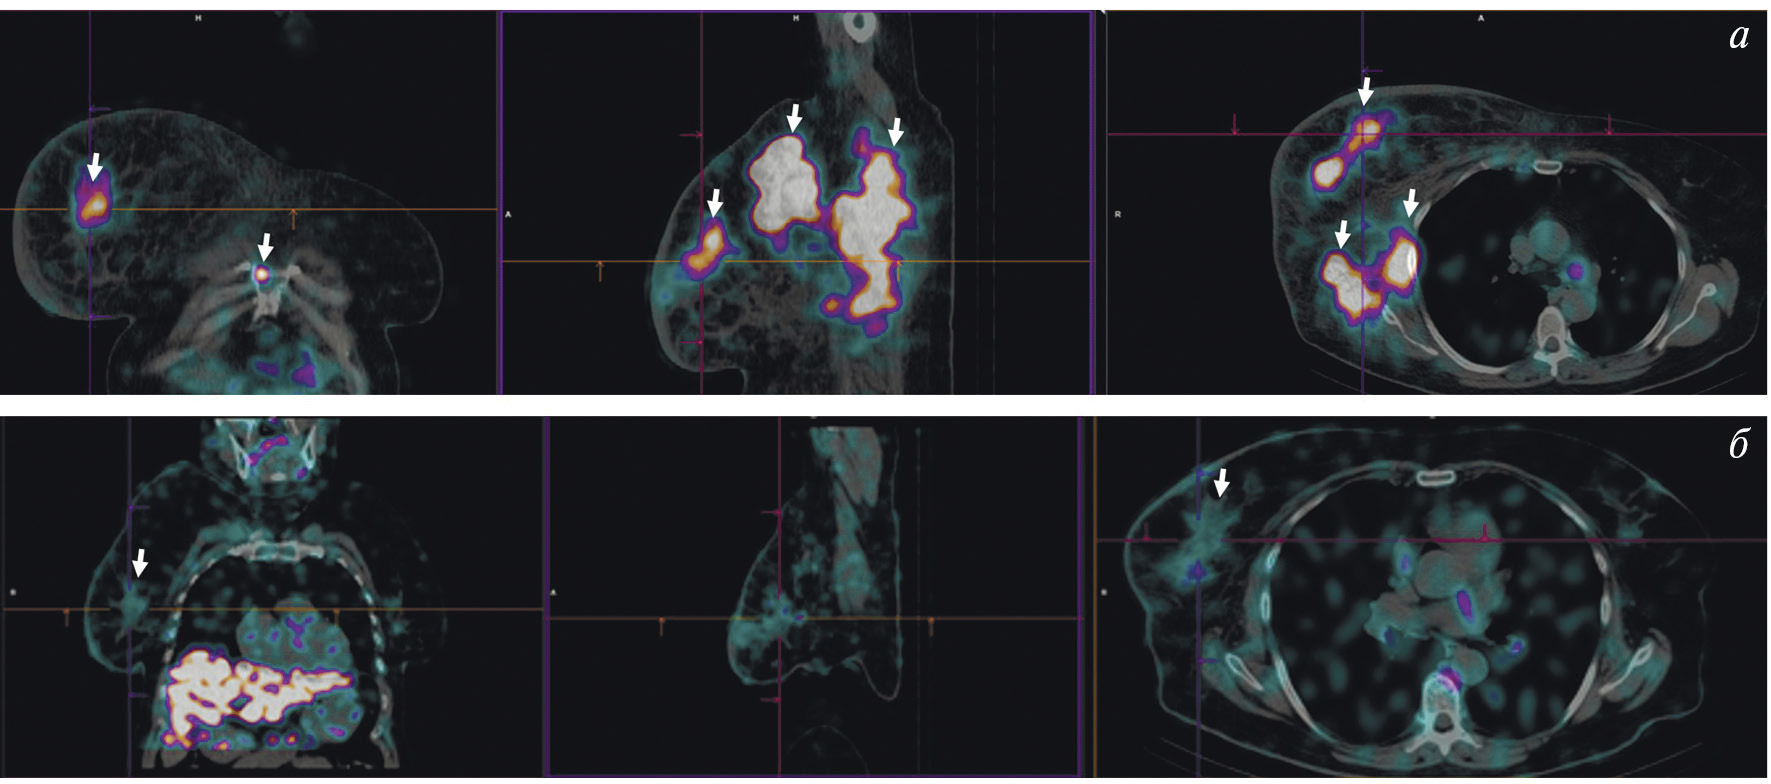

В НИИ онкологии Томского НИМЦ завершены первые фазы клинических исследований нескольких меченных технецием-99м каркасных белков (DARPin, ADAPT, Affibody), обладающих высокой аффинностью к рецептору эпидермального фактора роста второго типа (HER2/neu). Все препараты показали хорошую эффективность определения гиперэкспрессии рецептора HER2/neu при раке молочной железы и стадировании заболевания (рис. 1) [10, 11]. Кроме того, установлена возможность проведения ОФЭКТ/КТ с препаратами на базе скаффолдов для оценки эффекта терапии (рис. 2). Помимо основы РФЛП для диагностики злокачественных новообразований, каркасные белки могут служить вектором доставки при создании таргетных соединений для лечения злокачественных новообразований с гиперэкспрессией рецептора HER2/neu [13].

Рис. 1. ПЭТ-изображение пациентки с HER2/neu-позитивным раком молочной железы, выполненное через 5 суток после введения 89Zr-транстузумаба (a), стрелками обозначены метастазы в печень и кости [12]; ОФЭКТ-изображение пациентки с HER2/neu-позитивным раком молочной железы через 2 ч после введения 99mTc-ADAPT6 (б), стрелками обозначены первичная опухоль, метастазы в лимфатические узлы, печень и кости

Рис. 2. ОФЭКТ/КТ-изображение пациентки с HER2/neu-позитивным раком правой молочной железы до начала лечения, выполненное через 2 ч после введения 99mTc-DARPIN-G3 (а), стрелками обозначены первичная опухоль (SUVmax = 3.1), метастазы в лимфатические узлы (SUVmax = 8.8) и кости; ОФЭКТ/КТ-изображение той же пациентки после двух курсов терапии транстузумабом через 2 ч после введения 99mTc-DARPIN-G3 (б), стрелками обозначена первичная опухоль (SUVmax = 0.55), метастазы не визуализируются